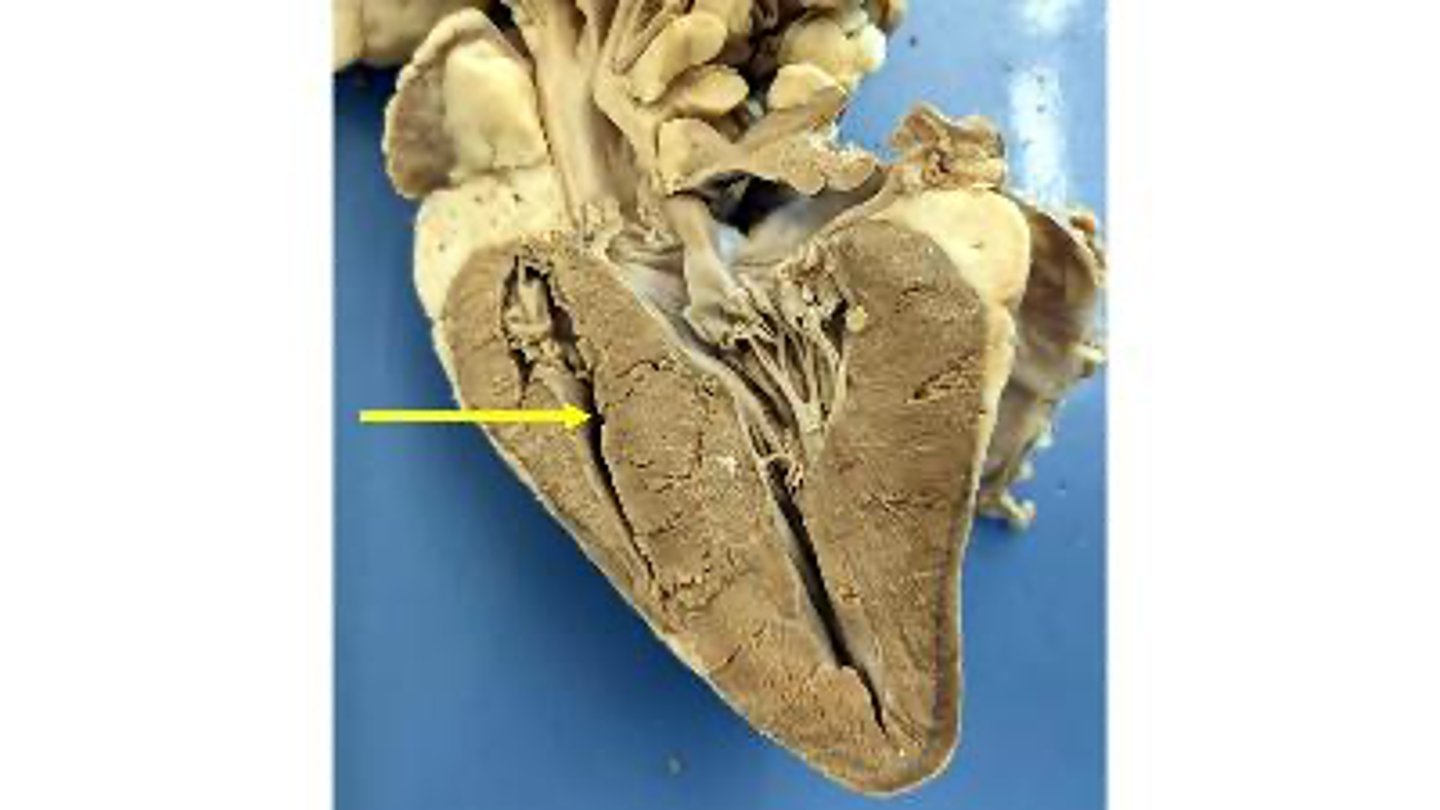

left ventricle

Name the chamber

interventricular septum

Name the dividing wall indicated

chordae tendineae

Name the structures

right ventricle

endocardium

Name the membrane

myocardium

Name the Layer